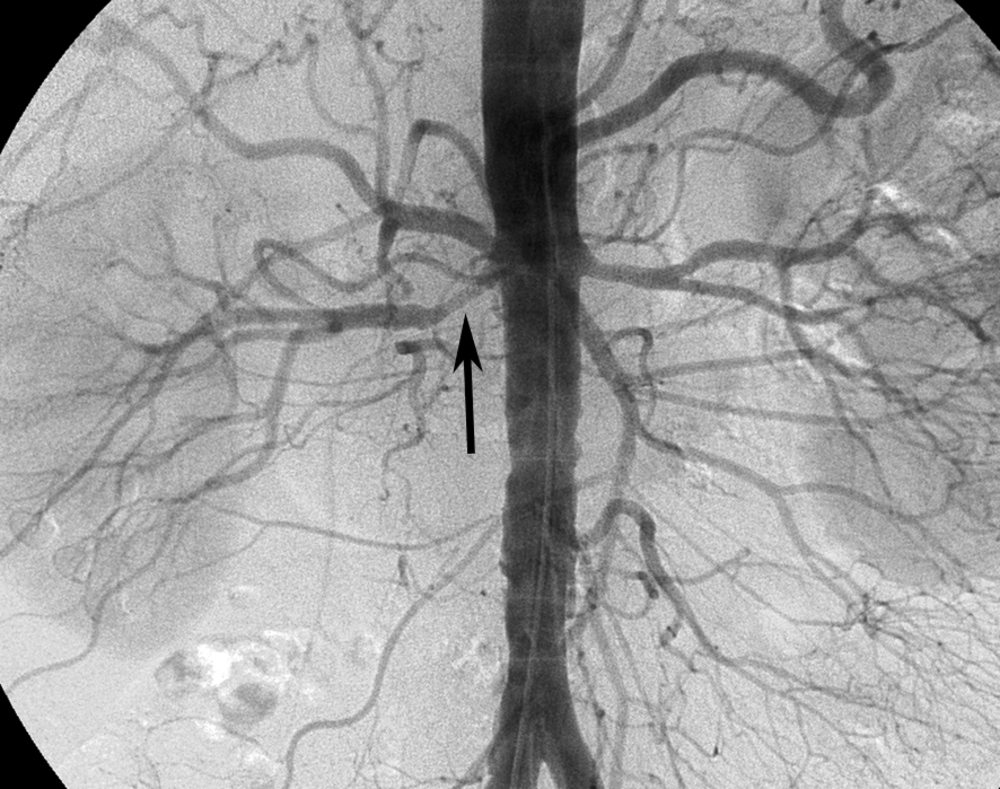

- Аортография – это метод, который позволяет изучить состояние аорты с помощью введения контрастного вещества и последующей видеозаписи. Данная процедура помогает выявить наличие уплотнений, аневризм и кальцинозов.

- Ангиография – это группа методов контрастного исследования сосудов, применяемая в рентгенографии, рентгеноскопии, компьютерной и магнитно-резонансной томографии, а также в гибридных операционных. Она позволяет обнаружить нарушения кровотока в определенной области. Введение специального контрастного вещества помогает визуализировать измененные участки.

- Коронарография – это рентгеноконтрастный метод, который считается наиболее точным и надежным для диагностики ишемической болезни сердца. Он позволяет определить характер, локализацию и степень сужения коронарной артерии.